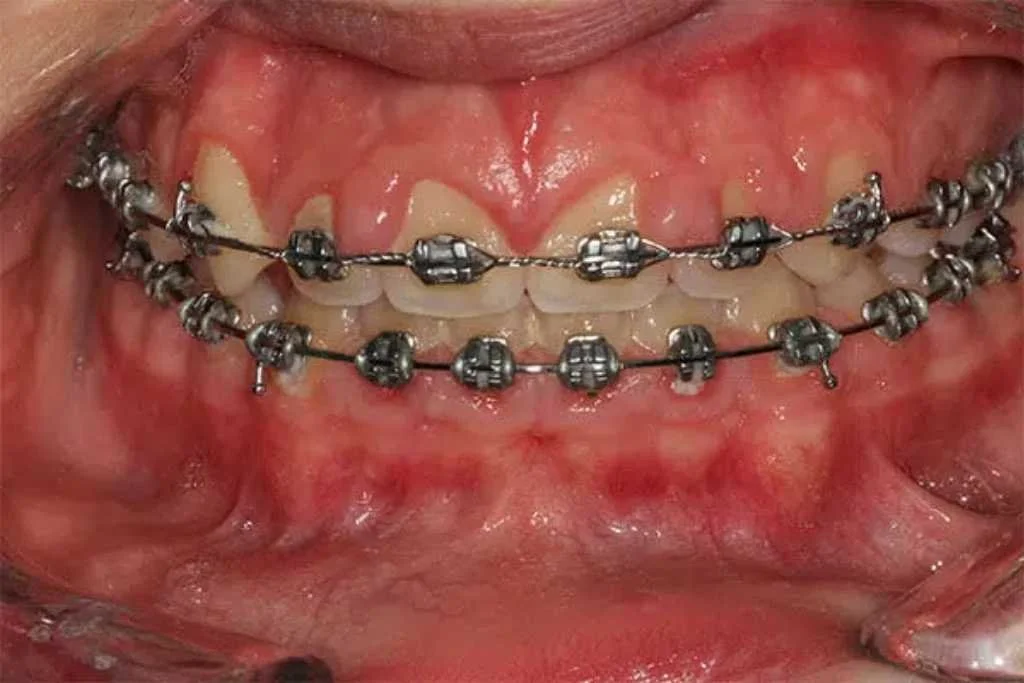

Close-up image of a normal teeth with braces.

One reason by people develop gummy smiles is inflammation and bleeding of the gums caused by bacteria. Gum disease (gingivitis and periodontitis) can result in gum tissue swelling, overgrowing, and starting to bleed. Braces and other orthodontic appliances can trap food and if proper oral hygiene is not done, can result in gum overgrowth (Figure 1). The first step is to start performing good oral hygiene and get dental cleanings. In many instances, surgical removal of excess gingival tissue may be needed which can be accomplished quickly and efficiently with a dental laser (figure 2).

Close-up of teeth with braces showing a gummy smile with excess gum tissue.

Gummy smile caused by a combination of poor oral hygiene and orthodontics increasing bacterial accumulation leading to gum overgrowth